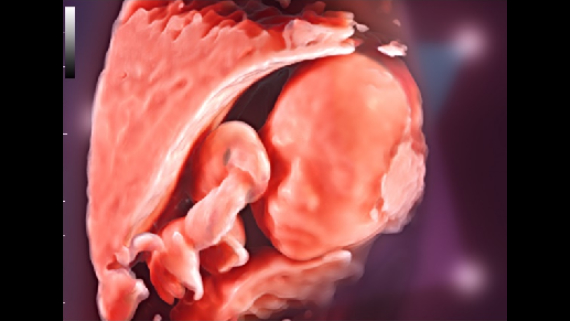

–°–Њ–≤–Љ–µ—Б—В–љ–Њ —Б —Б–Њ–≤—А–µ–Љ–µ–љ–љ—Л–Љ–Є —Г–ї—М—В—А–∞–Ј–≤—Г–Ї–Њ–≤—Л–Љ–Є —В–µ—Е–љ–Њ–ї–Њ–≥–Є—П–Љ–Є –љ–Њ–≤–Њ–µ —А–µ—И–µ–љ–Є–µ –Њ—В Mindray –њ—А–µ–Њ–±—А–∞–Ј—Г–µ—В –∞–Ї—В—Г–∞–ї—М–љ—Л–µ –Ј–∞–і–∞—З–Є –Ї–ї–Є–µ–љ—В–Њ–≤ –≤ –Ї–ї–Є–љ–Є—З–µ—Б–Ї–Є–µ –њ–Њ—В—А–µ–±–љ–Њ—Б—В–Є.

–Ю—Б–љ–Њ–≤—Л–≤–∞—П—Б—М –љ–∞ –≥–ї—Г–±–Њ–Ї–Њ–Љ –њ–Њ–љ–Є–Љ–∞–љ–Є–Є –њ–Њ—В—А–µ–±–љ–Њ—Б—В–µ–є –Ї–ї–Є–µ–љ—В–Њ–≤, –Ї–Њ–Љ–њ–∞–љ–Є—П Mindray —А–∞–Ј—А–∞–±–Њ—В–∞–ї–∞ —Б–Є—Б—В–µ–Љ—Г DC-70 Exp —Б X-Insight, —З—В–Њ–±—Л –Њ–±–µ—Б–њ–µ—З–Є—В—М eXpress Clarity, eXceptional Intelligence, eXceeding Experience.